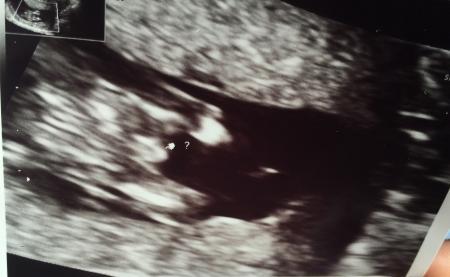

Hallo:) 12+1 Was meint ihr kann man so früh überhaupt was sagen? Liebe Grüße

Ich würde sagen nein. In der Woche sehen die Geschlechter noch eher gleich aus. Beim Mädchen wächst es dann rein und beim jungen bleibt es so

Ich denke auch eher nein:) der Arzt war sich allerdings glaub ich sehr sicher das es ein Junge ist.

Denke das des n bissi zu früh is um zu sagen ob mädel oder bub... warte lieber noch 2-3 wochen dann isses denke ich mal eher zu unterscheiden ...

Unmöglich ist es nicht, denke ich.unterscheidet sich ja schon am Winkel, in dem es absteht... Bei jungen ist es auch einfacher zu erkennen. Eine Bekannte hatte ihr jungenouting auch in der 13. SSW und es stimmte. Aber bevor du shoppen gehst, warte lieber mal den nächsten Termin ab :)

Das ist möglich. Meine beiden wurden auch jeweils in der 13. Woche geoutet. Das Kind muss nur von der Seite geschalt werden und es muss dafür auf dem Rücken liegen. Wenn der knubbel nach oben absteht, ist es ein junge, nach unten, flach, ein Mädchen. Aber es ist nicht so sicher, natürlich. Und es können nur die fachÄrzte feststellen, weil die normale FrauenÄrzte dafür nicht ausgebildet sind

Ja, aber ich verstehe es nicht so richtig. Ist es von oben zwischen den Beinen geschaut, oder?

Von unten glaub ich. Aber wo hat er oder sie die Unterschenkel versteckt